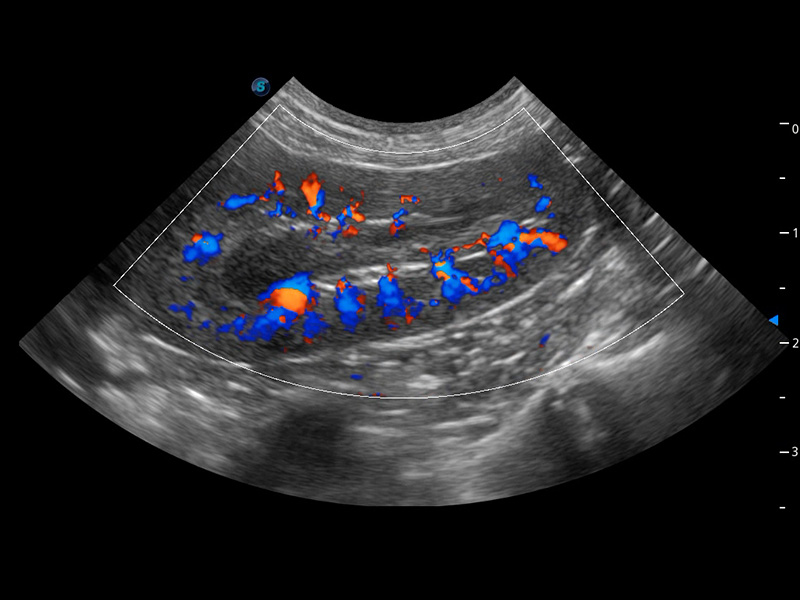

ProPet 60 作为一款高端台式动物超声设备,为动物医生的日常诊断提供了一系列贴合动物临床需求、解决临床实际问题的高级成像功能。凭借全系列高清探头,满足医生对腹部、心脏、生殖、浅表、肌骨等成像的所有需求,切实帮助您提升检查效率,提高诊断信心。

动物是人类最亲密的朋友和最值得信赖的伙伴。亚星官网也一直致力于探索动物专用的超声影像解决方案。 全新推出的ProPet系列,是亚星官网在动物超声影像智能化、专业化、精准化的一次跨越式革新。动物不能用言语来表述自己的不适,通过超声影像,ProPet系列搭建了动物医生与不同物种沟通的“桥梁”,为动物医生注入了“治愈之力”。